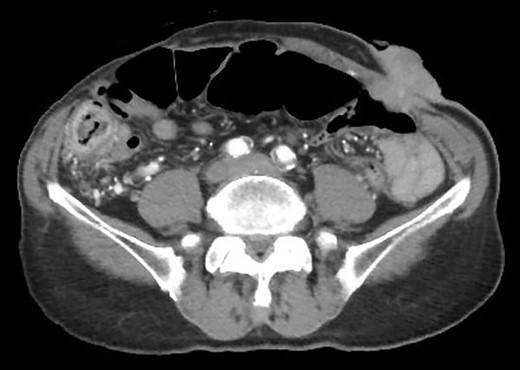

Contrast-enhanced computed tomography revealed a giant irregular mass (45 × 35 mm) in the abdominal wall (Fig. 2). No other intra-abdominal neoplasm were present; however, an irregular lung mass measuring 50 mm in size in the S10 region of the right lobe and a mass measuring 12 mm in size in the S1/2 region of the left lobe were found (Fig. 3). Total gastrointestinal endoscopy, including capsule endoscopy, revealed no neoplasm in the intestinal tract (Fig. 4a–c).

Computed tomography showed irregular mass at the abdominal wall.